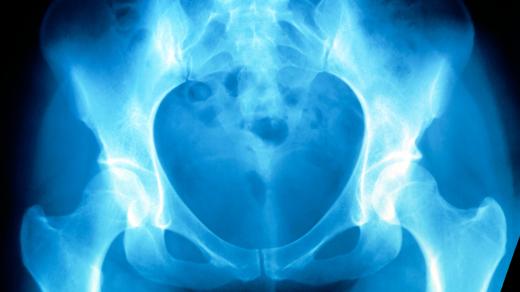

V dnešní radioporadně se věnujeme zánětlivému onemocnění zvanému psoriatická artritida, které postihuje kůži a klouby. Zjistíme, kdy zpozornět, jestli je nemoc infekční, jak vypadá léčba a její novinky a jestli je chronickému zánětu možné předcházet? Pozvání do studia přijal doc. MUDr. Petr Bradna, revmatolog Fakultní nemocnice Hradec Králové.